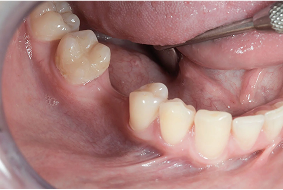

kiedy stosuje się implanty?

Brak pojedynczego zęba

Brak kilku zębów

Całkowity brak uzębienia

Wskazaniem do leczenia implantologicznego jest już każdy brak zęba, nawet brak pojedynczego zęba, kilku, jak i całkowity brak uzębienia. Takie implanty najlepiej wszczepić jak najszybciej i jest to możliwe nawet w dniu usunięcia zęba. Czas od ekstrakcji do wprowadzenia implantu uzależniony jest od stanu tkanek otaczających usuwany ząb. W sytuacji gdy przyczyną ekstrakcji jest stan zapalny, odraczamy wprowadzenie nowego implantu nawet o kilka tygodni. Urazy i zniszczenia tkanek twardych zęba kwalifikujące go do usunięcia umożliwiają wczesne i natychmiastowe wszczepienie implantu. Warunkiem prawidłowego wszczepienia implantu jest obecność kości niezbędnej do prawidłowego zakotwiczenia wszczepu. Niewystarczająca ilość kości uniemożliwia wprowadzenie implantu we właściwej pozycji, co zmusza nas do wykonania dodatkowego zabiegu regeneracji kostnej, który poprzedza o kilka miesięcy wszczepienie implantu zęba.

Ekstrakcja zęba i natychmiastowe wszczepienie implantów zębowych w jego miejsce jest możliwe, jeśli tylko lekarz stwierdzi, że są ku temu sprzyjające okoliczności. Przy kwalifikacji do takiego zabiegu chodzi głównie o ilość i dobrą kondycję kości, jak również tkanki miękkie (dziąsła) oraz brak stanu zapalnego w miejscu implantacji.